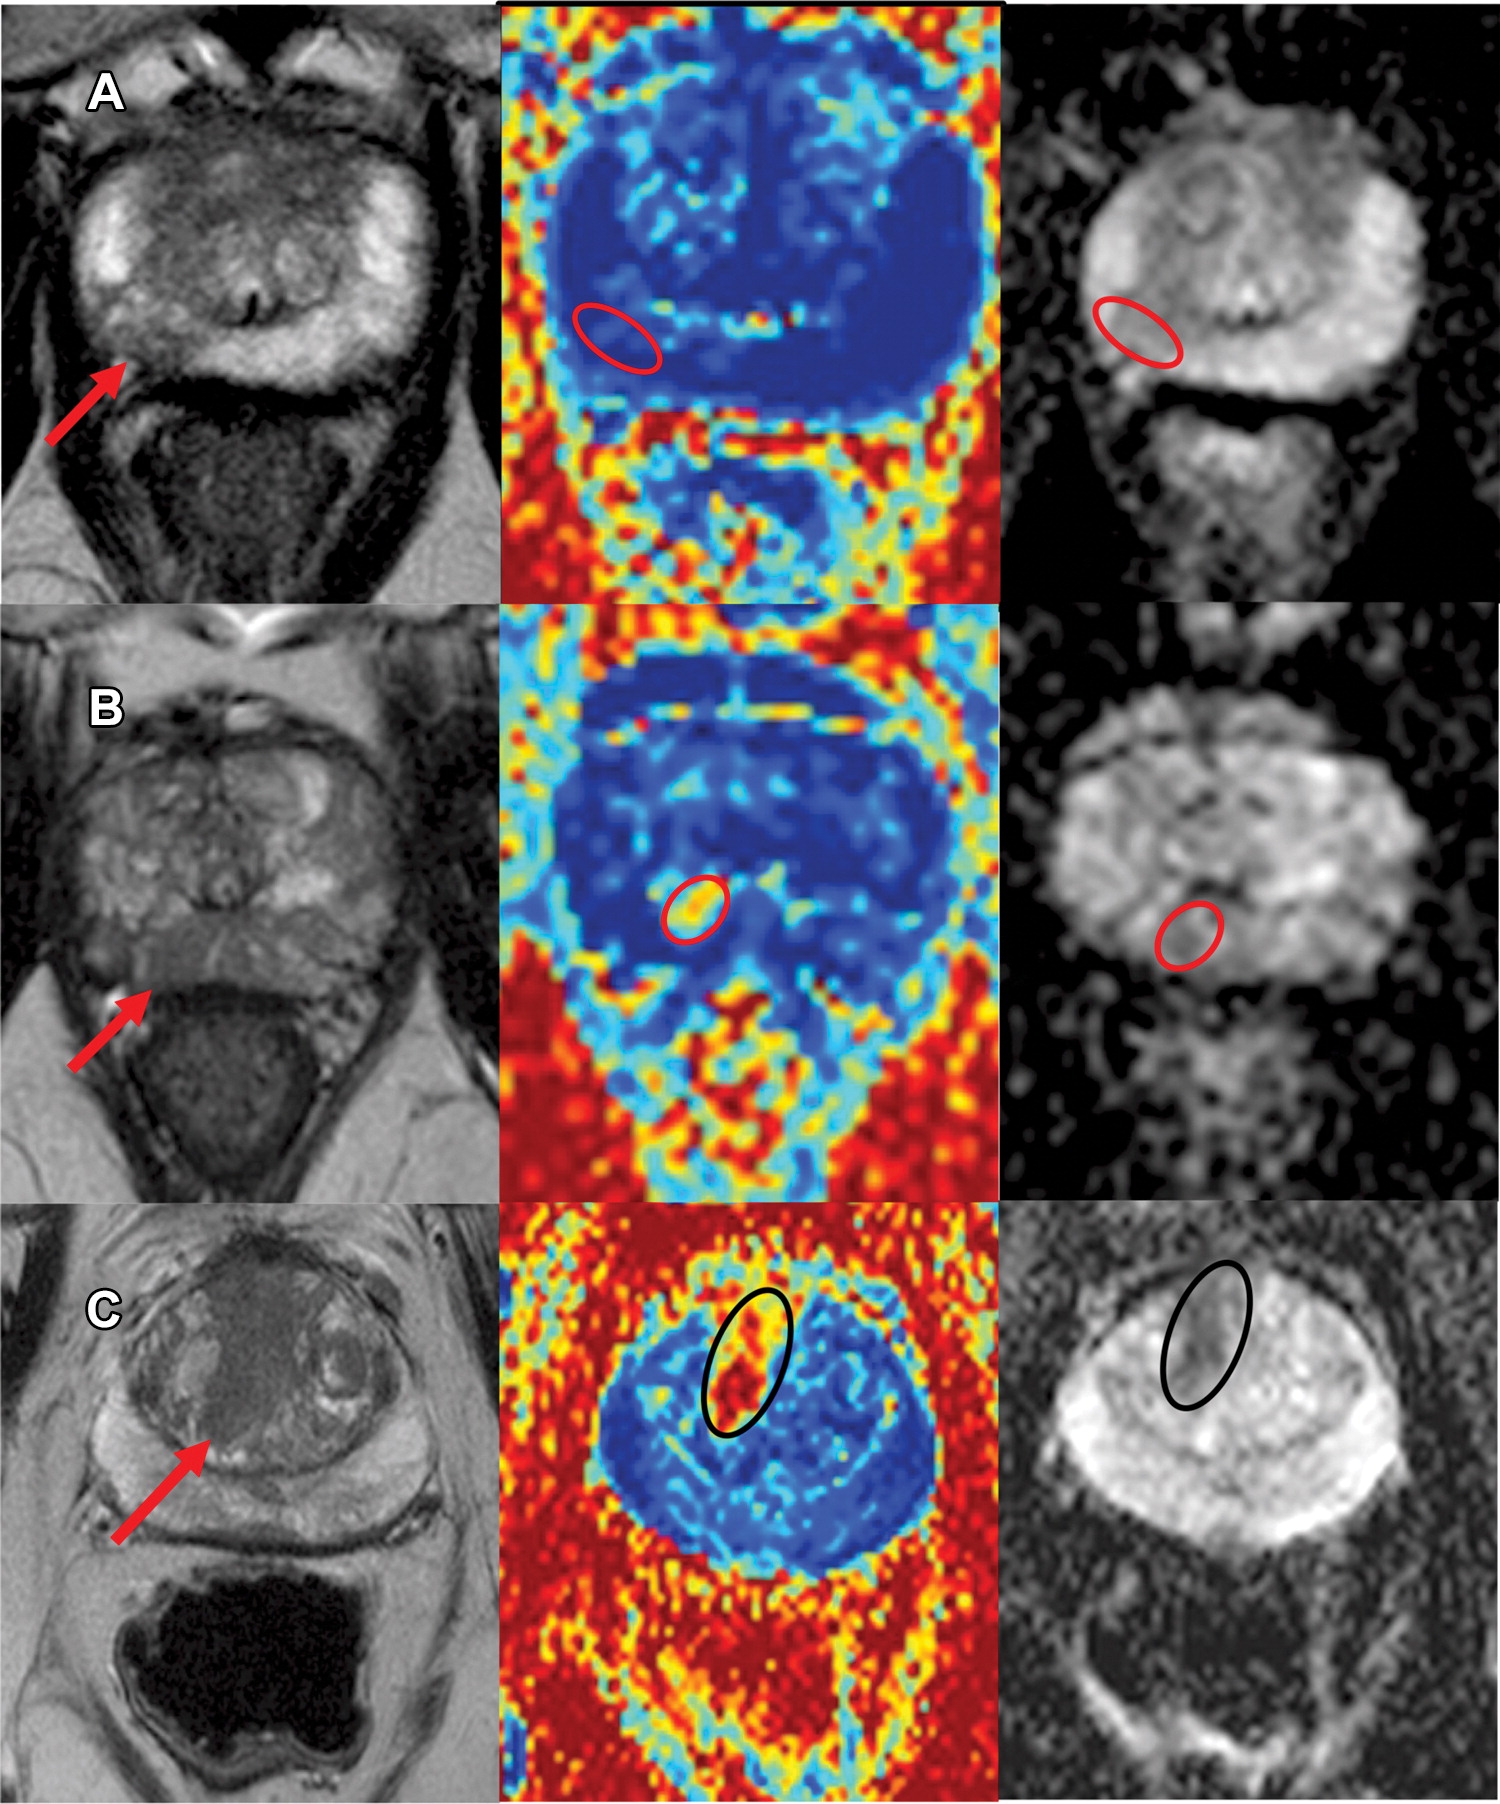

This work presents a biophysical model of diffusion and relaxation MRI for prostate called relaxation vascular, extracellular and restricted diffusion for cytometry in tumours (rVERDICT). The rVERDICT model allows for accurate, fast and repeatable estimation of diffusion and relaxation properties of PCa sensitive enough to discriminate Gleason grades 3+3, 3+4 and larger or equal to 4+3.

Marco Palombo, Vanya Valindria, Saurabh Singh, Eleni Chiou, Francesco Giganti, Hayley Pye, Hayley C. Whitaker, David Atkinson, Shonit Punwani, Daniel C. Alexander & Eleftheria Panagiotaki

In men suspected of having prostate cancer (PCa), up to 50% of men with positive multiparametric MRI (mpMRI) findings (Prostate Imaging Reporting and Data System [PI-RADS] or Likert score of 3 or higher) have no clinically significant (Gleason score ≤3+3, benign) biopsy findings. Vascular, Extracellular, and Restricted Diffusion for Cytometry in Tumor (VERDICT) MRI analysis could improve the stratification of positive mpMRI findings. We evaluate VERDICT MRI, mpMRI-derived apparent diffusion coefficient (ADC), and prostate-specific antigen density (PSAD) as determinants of clinically significant PCa (csPCa).

False positives on multiparametric MRIs (mp-MRIs) result in many unnecessary invasive biopsies in men with clinically insignificant diseases. This study investigated whether quantitative diffusion MRI could differentiate between false positives, true positives and normal tissue non-invasively.